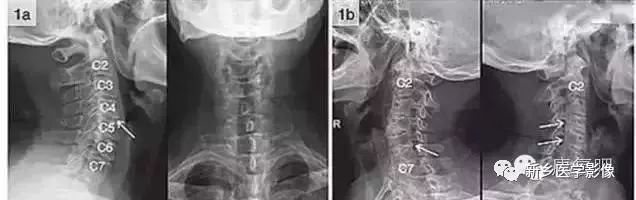

八孔:指椎间孔。实际上椎间孔是一个短管,故又叫椎间管,只是从X线平片上显示的是"孔"。管内含脊神经的前后根、神经节及节段性动脉、静脉等。主要从斜位片来观察椎间孔的影像变化。正常颈椎间孔呈长方形或椭圆形,高10mm,横径5mm,前后壁光滑。椎间隙变窄可造成椎间孔高度变小。椎间孔前后径变小是钩突增生、关节突增生、关节突关节肥大和椎体滑脱的结果。

如1a图示C4/5间隙狭窄,椎体后缘增生后翘,1b图示C5/6,C6/7双侧钩椎关节增生,椎间孔变窄

九突:指关节突关节。上位椎体的下关节突及下位椎体的上关节突构成关节突关节。若发生病变,可见关节间隙模糊,关节面粗糙、硬化,关节突关节间隙狭窄(2mm)和边缘骨刺。关节突关节半脱位多与椎体滑脱并存,侧位片上显示上关节突与上位椎体后缘重叠,关节间隙宽窄不一。